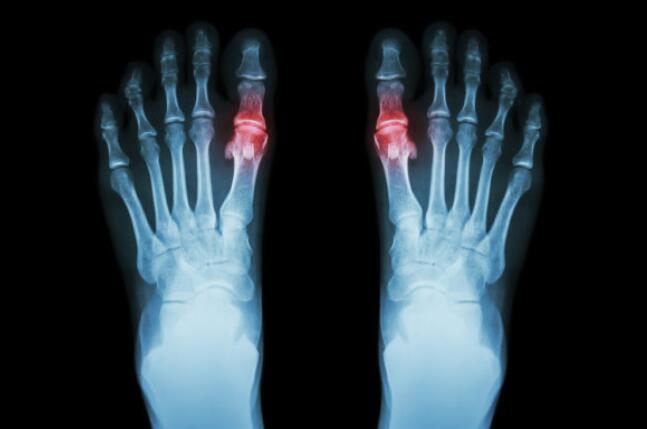

秋水仙碱是治疗痛风的药物,特别是用于急性痛风的治疗效果明显,已在临床应用多年,是一款经典老药。2020年12月30日,国家药品监督管理局发布公告指出,为保障公众用药安全,根据药品不良反应评估结果,决定对秋水仙碱片说明书进行统一修订。其中,特别要求添加“警示语”项,提示:“本品是细胞有丝分裂毒素,毒性大,一旦过量缺乏解救措施,须避免药物过量。”